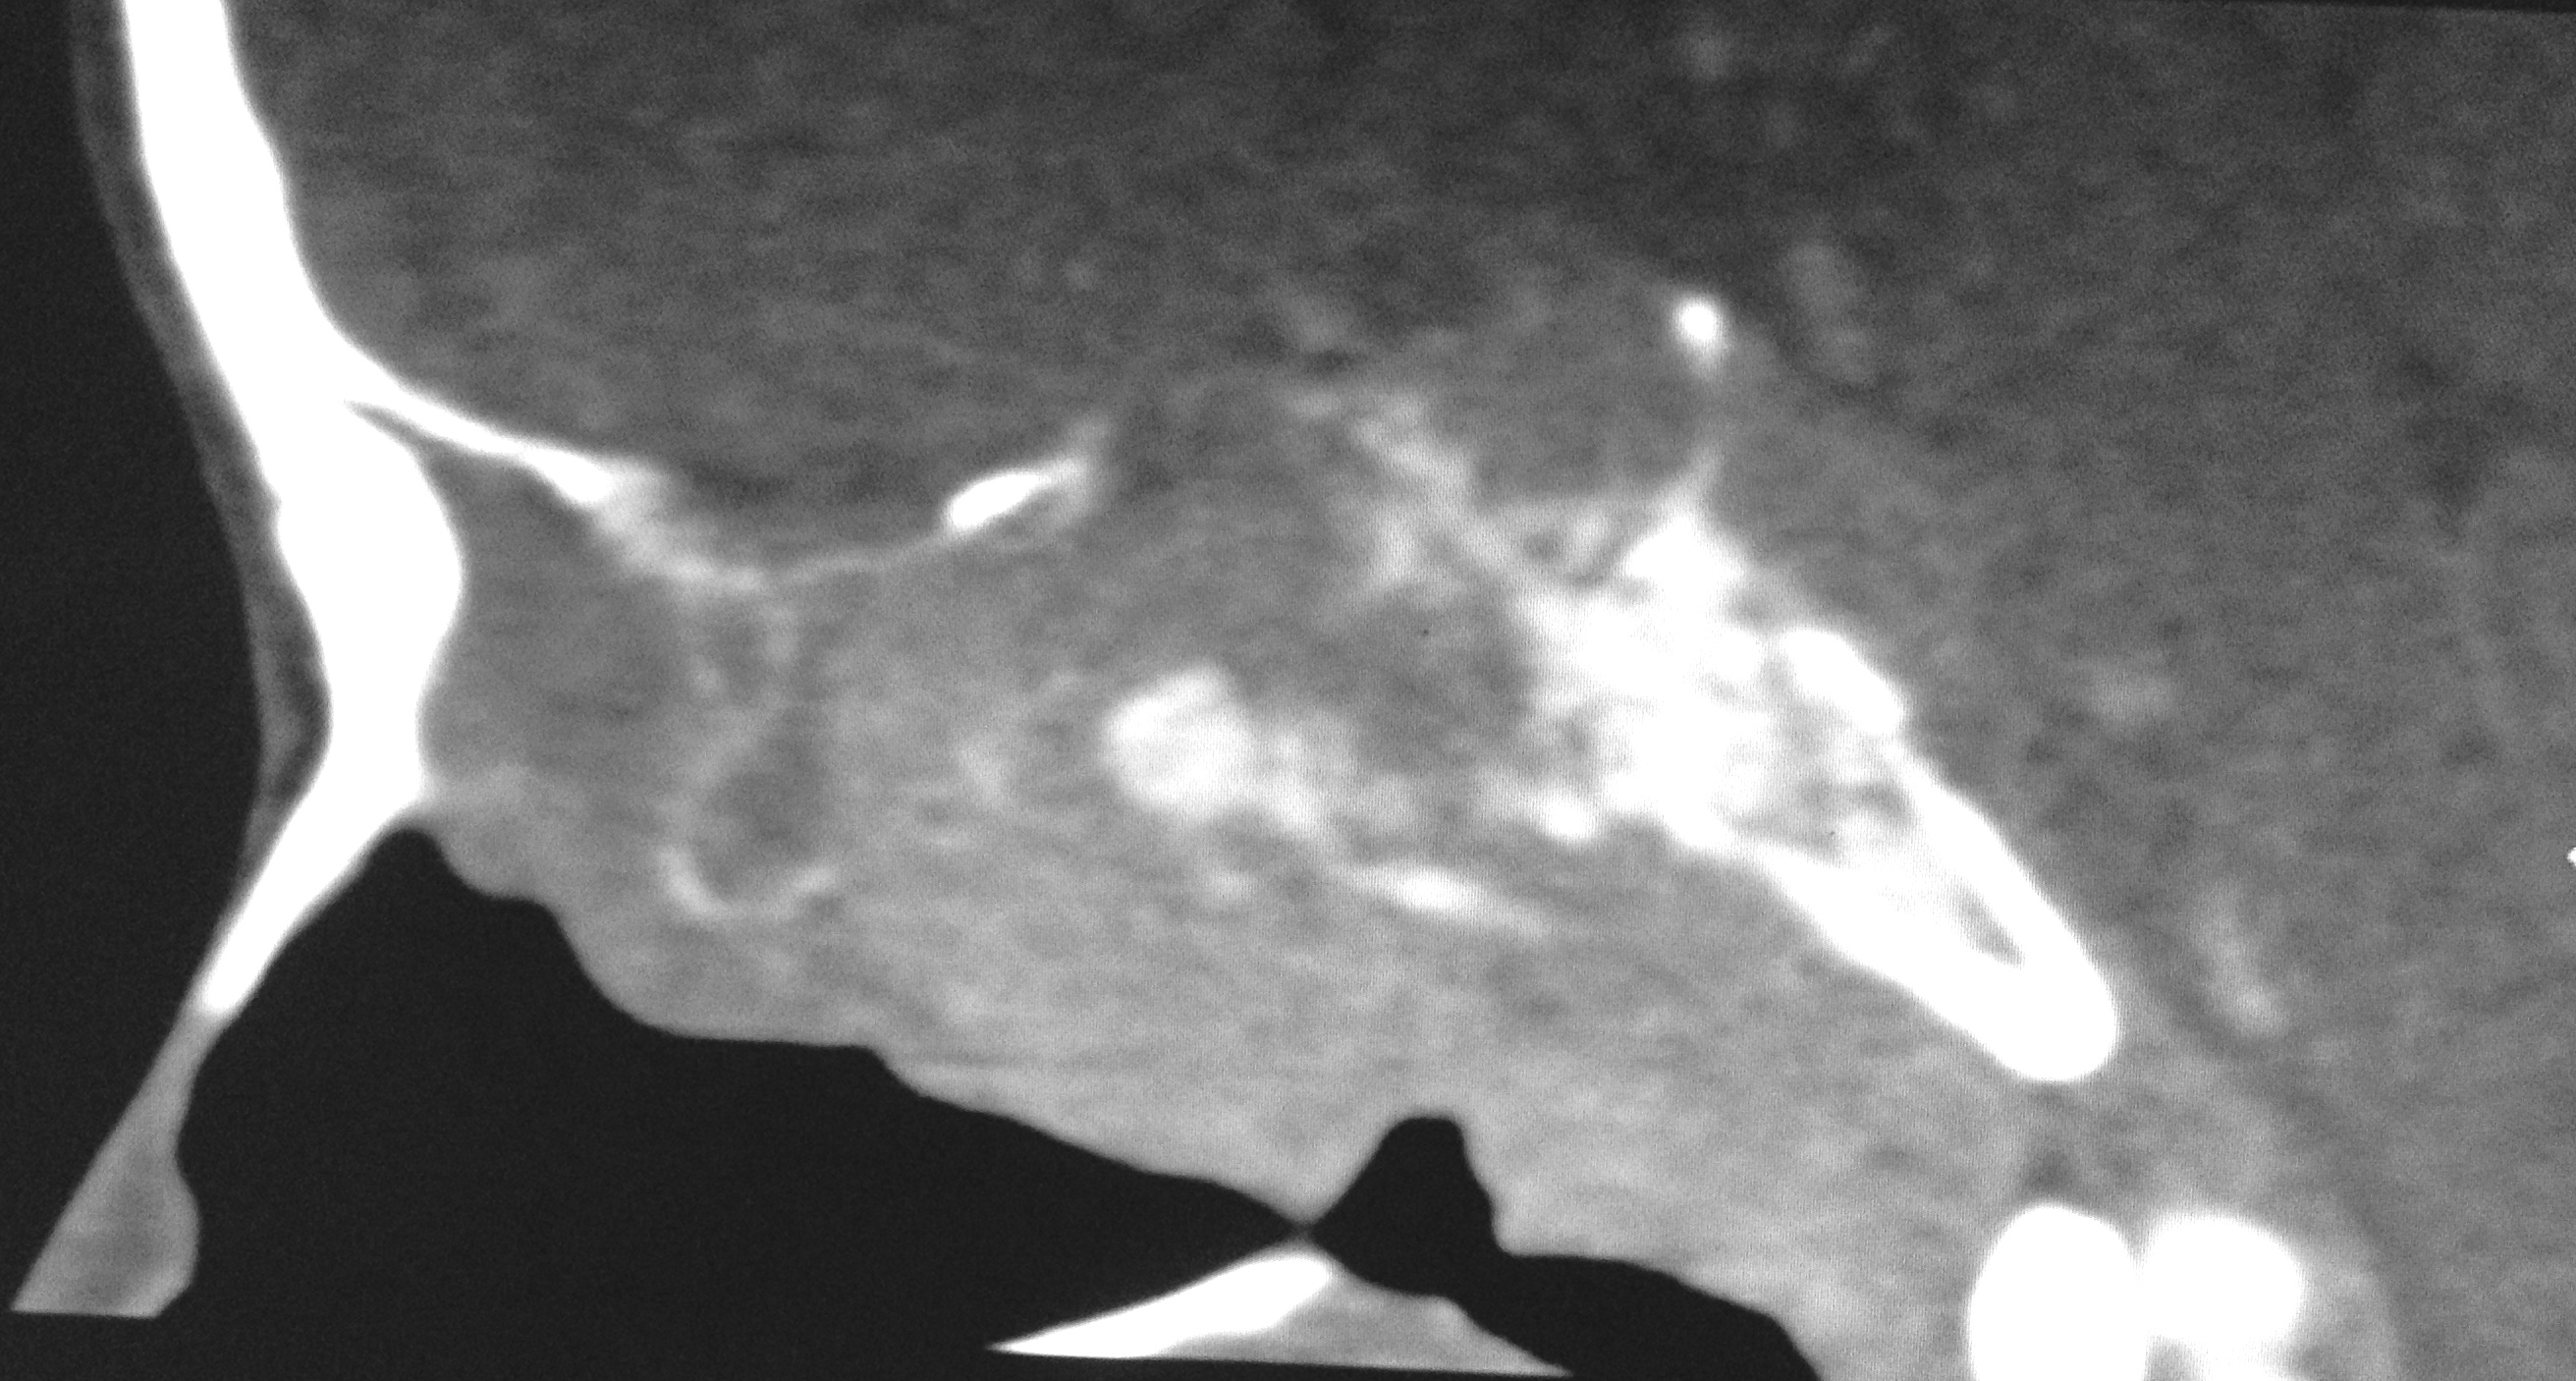

Nasopharyngeal carcinoma is a malignant disease and is more common in males than in females with M:F ratio of 3:1. It has a bimodal peak at 16-20 and 46-50 years of age. Orbital involvement is seen in 3.2% and bilateral orbital invasion occurs in 0.7% of patients with nasopharyngeal carcinoma. Imaging has significant role in detecting the early nasopharyngeal carcinoma, tumor staging, involvement of lymph node, monitoring the patients after the therapy, to detect recurrence and radiation associated changes in the soft tissue and bone. We report a case of aggressive nasopharyngeal carcinoma in 22 years old male who presented with rapidly progressive diminution of vision.